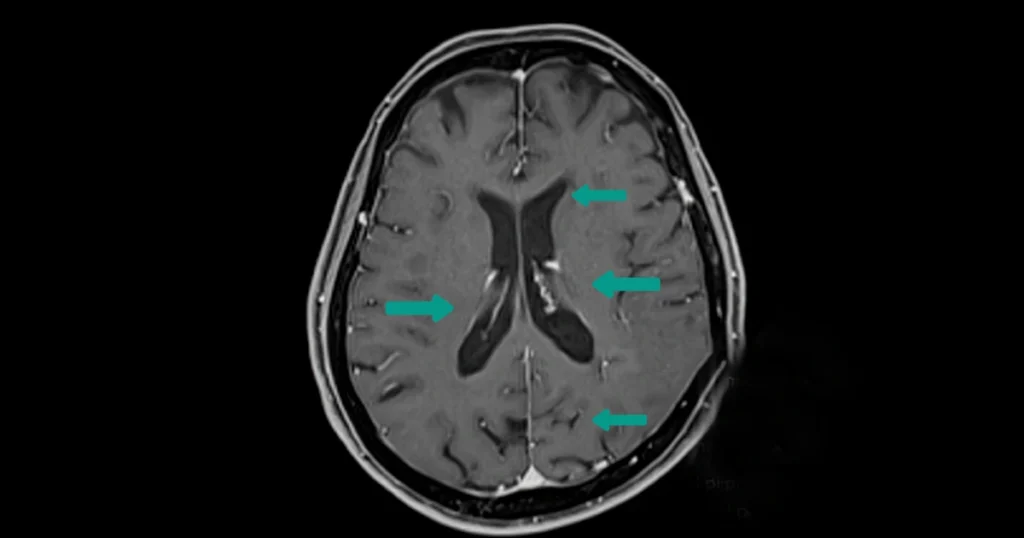

An MRI is one of the most important tools for diagnosing MS because it shows inflammation that isn’t always noticeable through physical exams. Neurologists pay close attention to brain lesions in multiple sclerosis, which often appear as bright spots on MRI scans. These lesions reflect areas where the immune system has damaged the protective coating around nerves.

Brain Lesions in Multiple Sclerosis

Brain lesions are a key marker of MS because they show areas where the immune system has damaged the myelin, the protective coating around nerve fibers. These lesions can appear in several regions, including the periventricular area, cerebellum, brainstem, and spinal cord. Their location often explains symptoms like numbness, poor coordination, or vision issues.

Understanding lesion activity helps neurologists determine how active the disease is. Over time, changes in lesion size or number can reveal whether treatments are slowing inflammation or if another medication may be necessary.